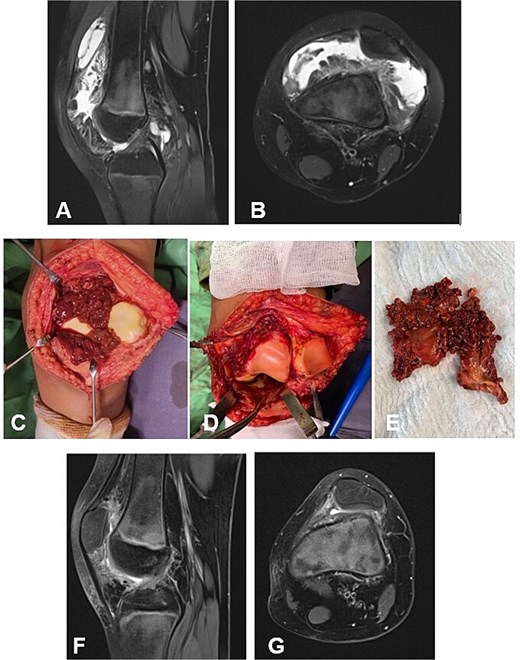

A 9-year-old female presented with a one-year history of knee pain, swelling, and progressive limitation of flexion, unresponsive to nonsteroidal anti-inflammatory drugs and physical therapy. MRI demonstrated a large anterior synovial mass without evidence of bone erosion (Fig. 3A and B). The D-TGCT involved the suprapatellar recess as well as the superior and inferior infrapatellar recesses (Fig. 3C). The pathologically altered synovium was excised en bloc through an open synovectomy (Fig. 3D and E). The hyaline cartilage changes were classified as Outerbridge grade I. At 18 months postoperatively, the patient was asymptomatic, exhibiting full range of motion in the knee. Follow-up MRI revealed no evidence of recurrence of the resected neoplasm (Fig. 3F and G).

Case 2. (A and B) Preoperative Sag and Ax MRI weighted TSE PD FS. (C and E) Macroscopic appearance of the pathological synovium before and after its excision. (D) The knee joint following synovectomy. Chondral lesions correspond to Outerbridge grade I. (F and G) Postoperative 16 m. Sag and Ax MRI TSE PD FS—no evidence of recurrence of the resected neoplasm. Persistent bone marrow edema, though without clinical symptoms. PD FS, proton density weighting with fat suppression; TSE, turbo spin echo.

Case 3

A 6-year-old girl with a 3-year history of knee pain and swelling, previously treated for Synovitis transitoria. The chronic course of the condition corresponded to progressive limitation of flexion and the development of a flexion contracture (Table 1). The diagnosis was established by MRI (Fig. 4A and B). The D-TGCT involved the central, superior, and inferior infrapatellar synovial recesses (Fig. 4C). Through open synovectomy, the visibly altered synovium was excised en bloc (Fig. 3D and E). The hyaline cartilage changes were classified as grade I according to Outerbridge. One year after surgery, the child remained asymptomatic with a full range of motion in the knee. MRI showed no evidence of recurrence of the excised neoplasm (Fig. 3F and G).

Case 3. (A and B) Preoperative sag and ax MRI TSE PD FS. (C and E) Macroscopic appearance of the pathological synovium before and after its excision. (D) The knee joint following synovectomy. Chondral lesions correspond to Outerbridge grade I. (F and G) Postoperative 12 m. Sag and Ax MRI TSE PD FS—no evidence of recurrence of the resected neoplasm. PD FS, proton density weighting with fat suppression; TSE, turbo spin echo.